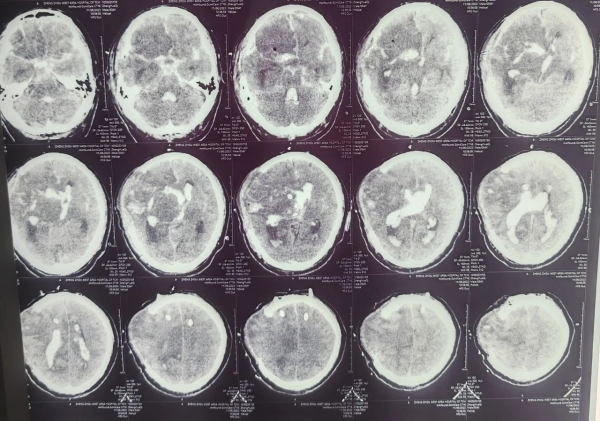

(術(shù)后1天)

(術(shù)后7天)